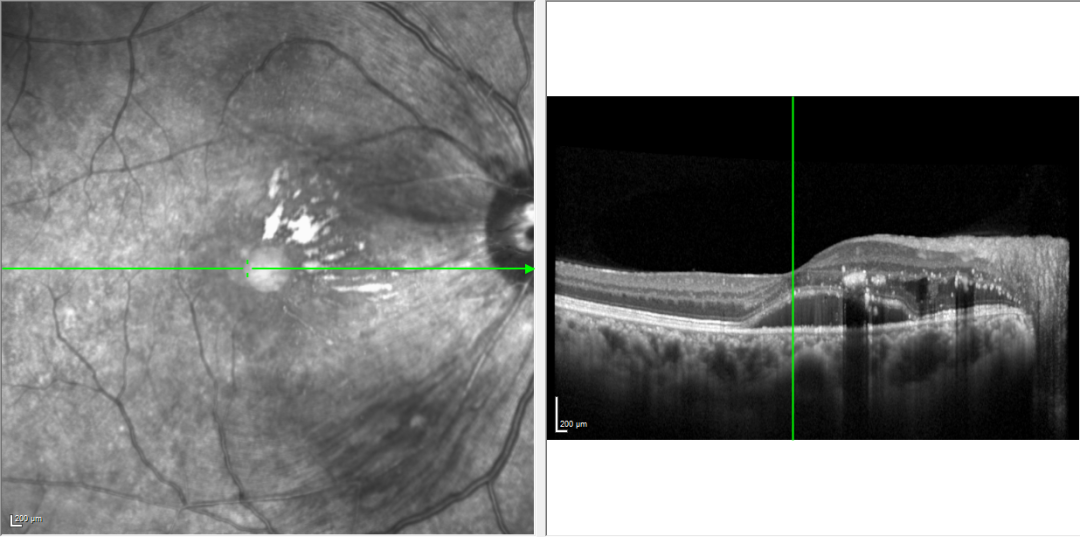

眼底彩照提示:双眼视网膜后极部大量黄色渗出,视网膜散在片状出血

OCT提示:双眼黄斑区视网膜可见团块状高反射,右眼黄斑区视网膜神经上皮层浅脱离,层间积液